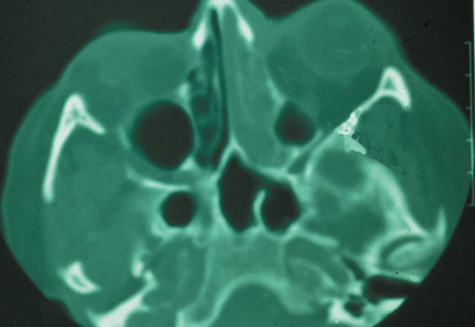

CT is particularly useful for imaging orbital and subperiosteal abscesses. Because the periorbit is not adherent to the orbital walls except at the suture lines, an abscess lifts the periorbit, creating a convexity in the orbital periosteum (Fig. 16). Usually subperiosteal abscess formation occurs adjacent to the involved sinus,25,64 but occasionally it occurs at a remote location such as the superolateral orbit.65 Gas may be found within a subperiosteal abscess or within the orbit, arising either from gas-forming bacilli or free communication with sinus air or from prior trauma (Fig. 17). 57,66 CT cannot accurately predict whether a subperiosteal mass represents exudate, inflammatory transudate, or hematoma.67,68

Fig. 16. Computed tomography showing subperiosteal abscess formation. Note elevation of orbital periosteum and convexity as pus elevates periorbit from the medial orbital wall.